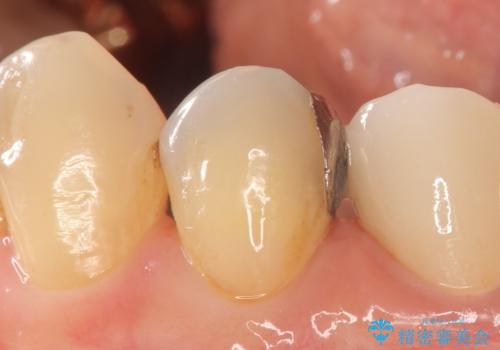

今回用いたオールセラミッククラウンはジルコニアフレームという白い素材の上にセラミックを盛っているため、審美性が非常に高いのが特徴です。

また、ジルコニアは人工ダイヤモンドの材料にも使われているほど高い強度を持っており、そのためオールセラミッククラウンは審美性だけでなく、奥歯やブリッジの補綴も可能とするクラウンです。